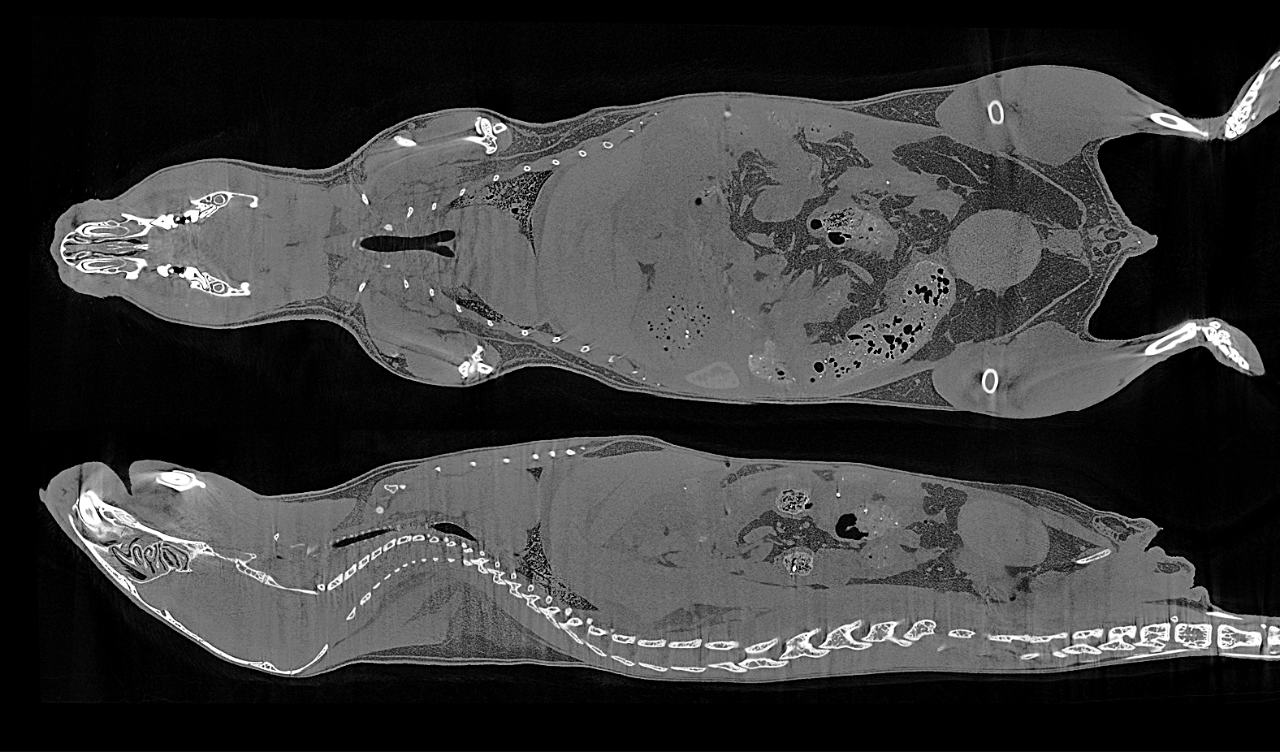

6. Cross-sectional slices through a mouse body, scanned at 17um voxel size in vivo without contrast agent injection.